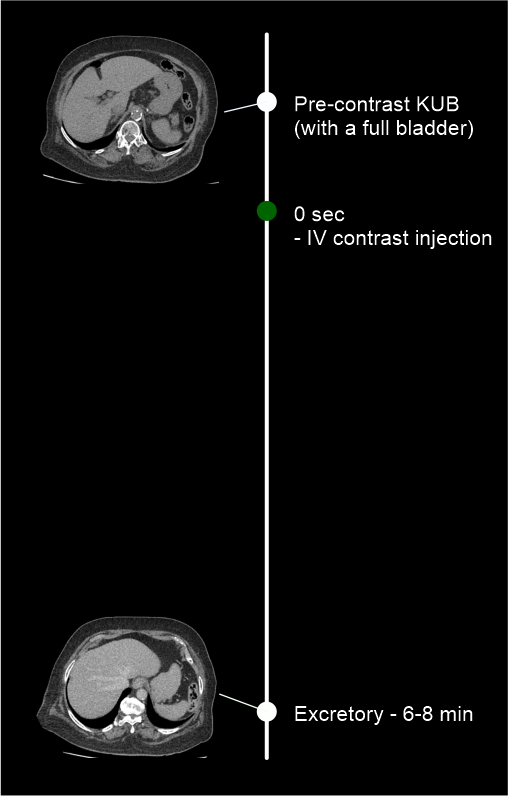

Pre-contrast and post-contrast steps are mandatory for this scan, but more steps may be added depending on the diagnostic needs of the patient.

Two step method simply can be used to diagnose stenosis in the ureters, but without suspectedneoplasms.

- Use time-bolus method for phase initiation – refer CT multiphase abdomen scan for more details.

- Plan both pre-contrast and excretory phases to cover from dome of the diaphragm to a level just below the ischial tuberosities.

Four step method is more suitable for patients with renal neoplasms.

- Use bolus-tracking method for phase initiation – reach CT multiphase abdomen scan for more information.

- Plan all pre-contrast, nephrogenic and excretory phases to cover from the mid-diaphram to a level below the ischial tuberosities.

- Plan corticomedullary phase to cover from the mid-diaphragm to the iliac crest.

In excretory phase, you can promote contrast flow into the distal part of ureters by scanning the patient in prone position because a slope is created from kidneys to bladder.